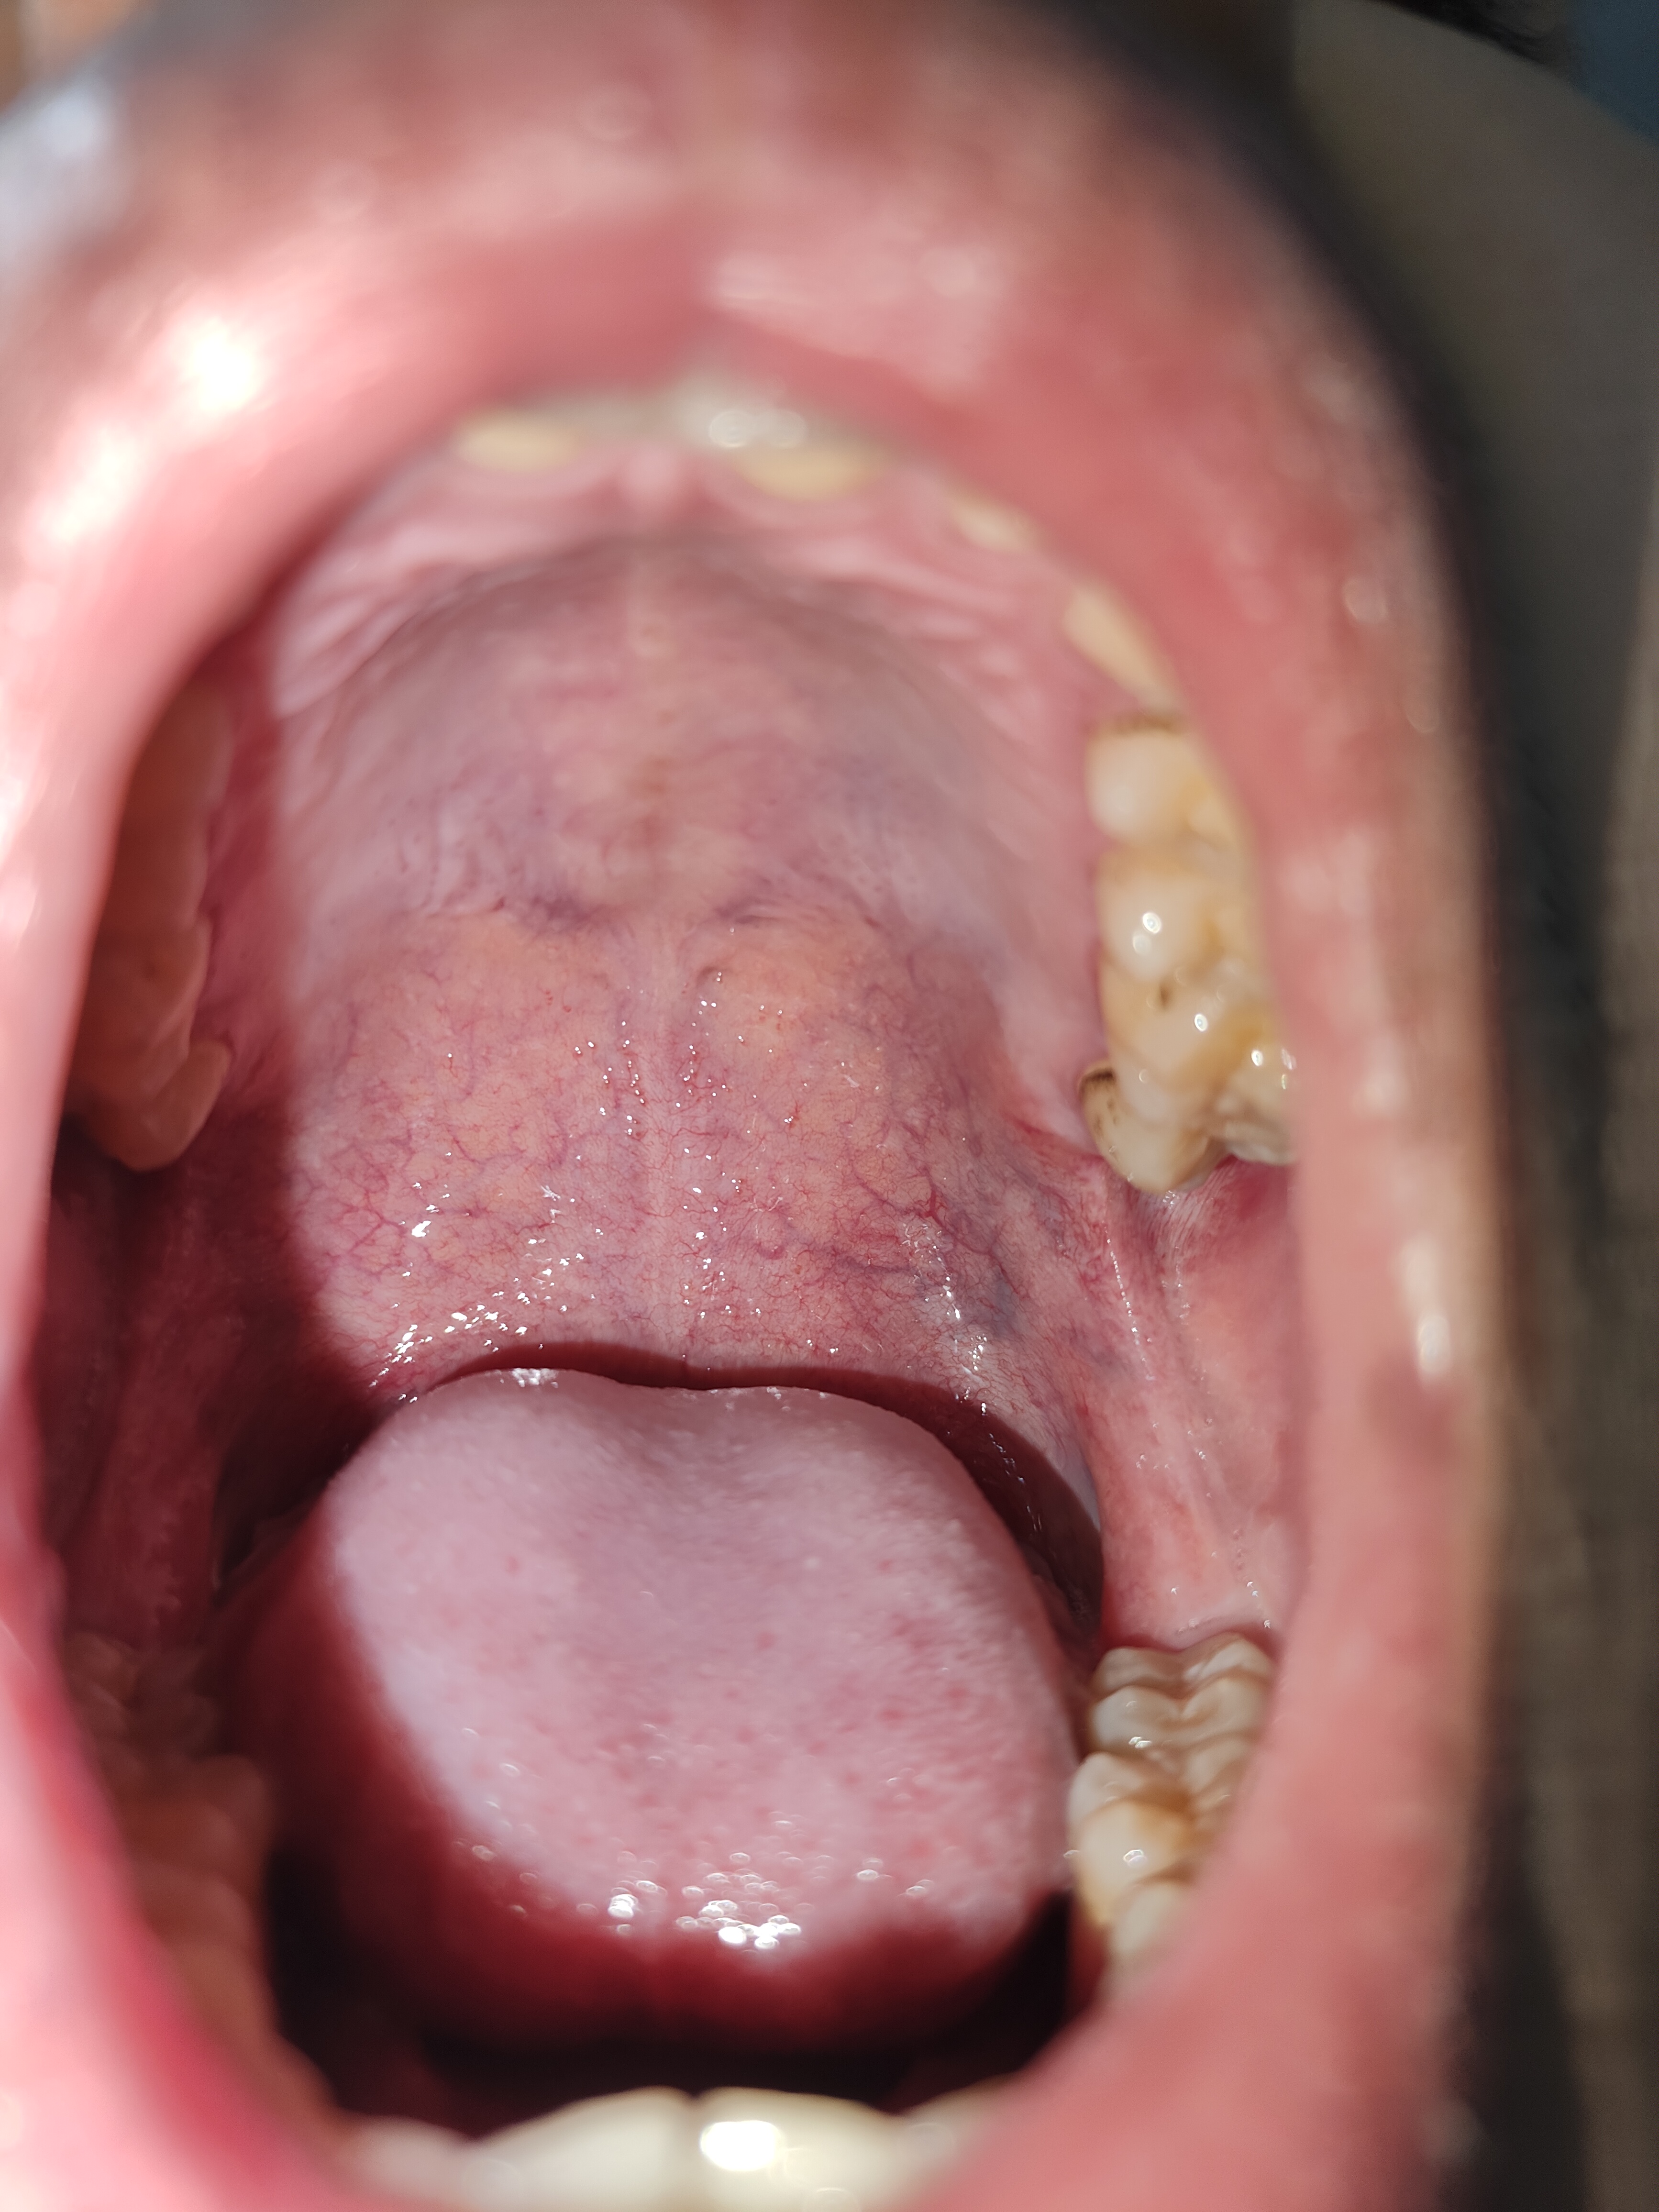

Chào bác sĩ, e có thấy mụn liti mọc ở vòm hòng và 1 con mụn ở khoang miệng trên, không biết có bị làm sao k ạ. Bác sĩ tư vấn giúp e với ạ

Hiện tại vòm họng sung huyết đỏ( giãn mao mạch). Thể hiện tình trạng viêm họng. Em nên súc họng nước muối sinh lý

Có thể ngậm viên giảm rát họng

Kiểm tra nhiệt độ xem sốt không